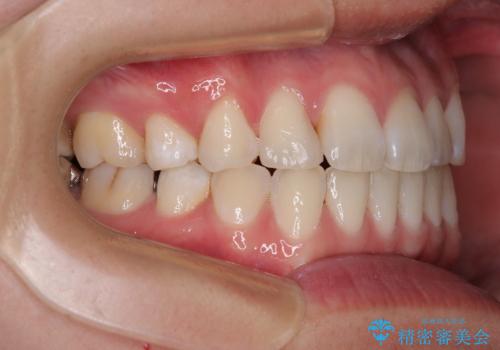

上下前歯のデコボコを気にして来院された患者様です。

舌の突出癖により、治療過程でスペースが多くできましたが、舌のトレーニングを頑張っていただき、1年強で終えることができました。